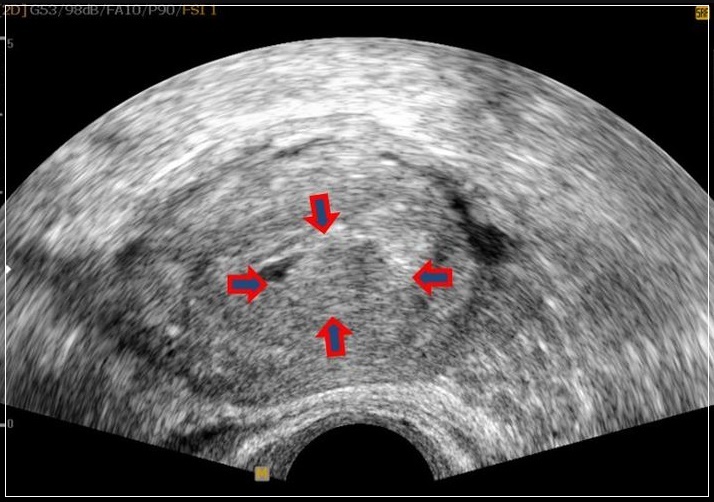

자궁,난소 등의 이상 소견을 확인하는 여성생식기 초음파 검사는 여성에서 흔히 발생하는 질환인 자궁근종, 난소 낭종 등을 진단하기 위한 기본적인 검사방법임에도 불구하고 그 동안 4대 중증질환(암·심장·뇌혈관·희귀난치)에 한해 제한적으로 건강보험이 적용됐 왔습니다.

특히나 자궁근종, 자궁내막증, 난소 낭종 등은 여성에서 흔히 발생하는 질환임에도 불구하고 건강보험이 적용되지 않았다. 전체 진료의 약 93%가 비급여로서 환자가 검사비 전액을 부담했습니다. 연간 비급여 규모는 약 3,300억 원으로 건강보험 적용 확대가 크게 요구되는 분야였습니다.